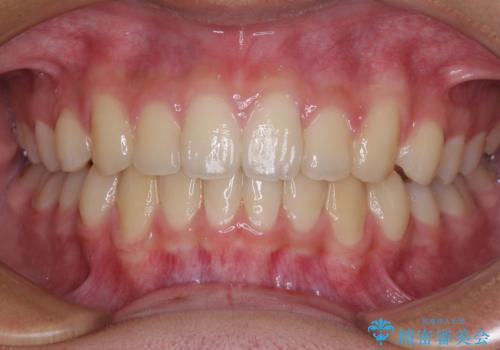

前歯の隙間とデコボコを改善 高校生のインビザライン治療

- 前歯のデコボコと隙間を気にして来院された高校生の患者様です。

下顎前歯が上顎前歯を突き上げるような咬み合わせとなっており、その影響で上顎正中に隙間ができている状態でした。

叢生の程度は軽度であり、本人もしっかりと使用する自信があるとのことだったので、インビザラインによる矯正治療を行うこととしました。

突き上げによる隙間を予防する為に、深い咬み合わせを改善するような治療計画としました。咬み合わせを改善させることはできましたが、隙間は後戻りしやすいので、通常の下顎前歯のみではなく、上顎前歯2本もワイヤーで保定を行いました。

高校生ということで、非常に短期間で治療を終えることができました。